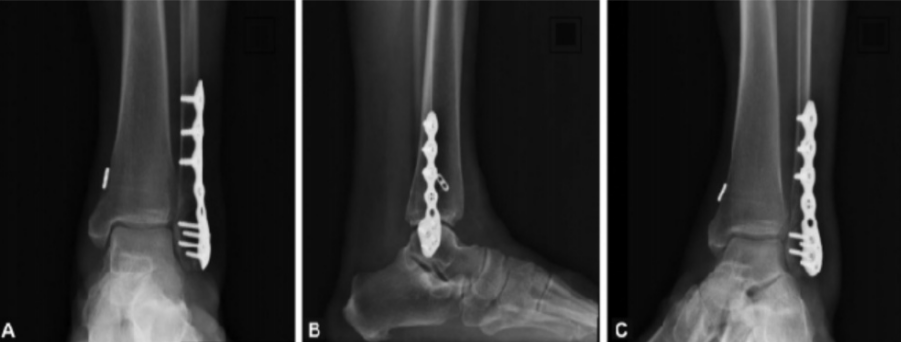

上图为患者术后X线片检查图像,外踝骨折行钢板螺钉固定,下胫腓联合损伤行带袢钢板固定。图A为正位片;图B为侧位片;图C为踝穴位片。(来自参考文献5)

上图为下胫腓联合损伤不同固定方式,图A-D患者行下胫腓螺钉内固定术;图E-H患者行下胫腓Endobutton带袢钢板内固定术。(来自参考文献2)